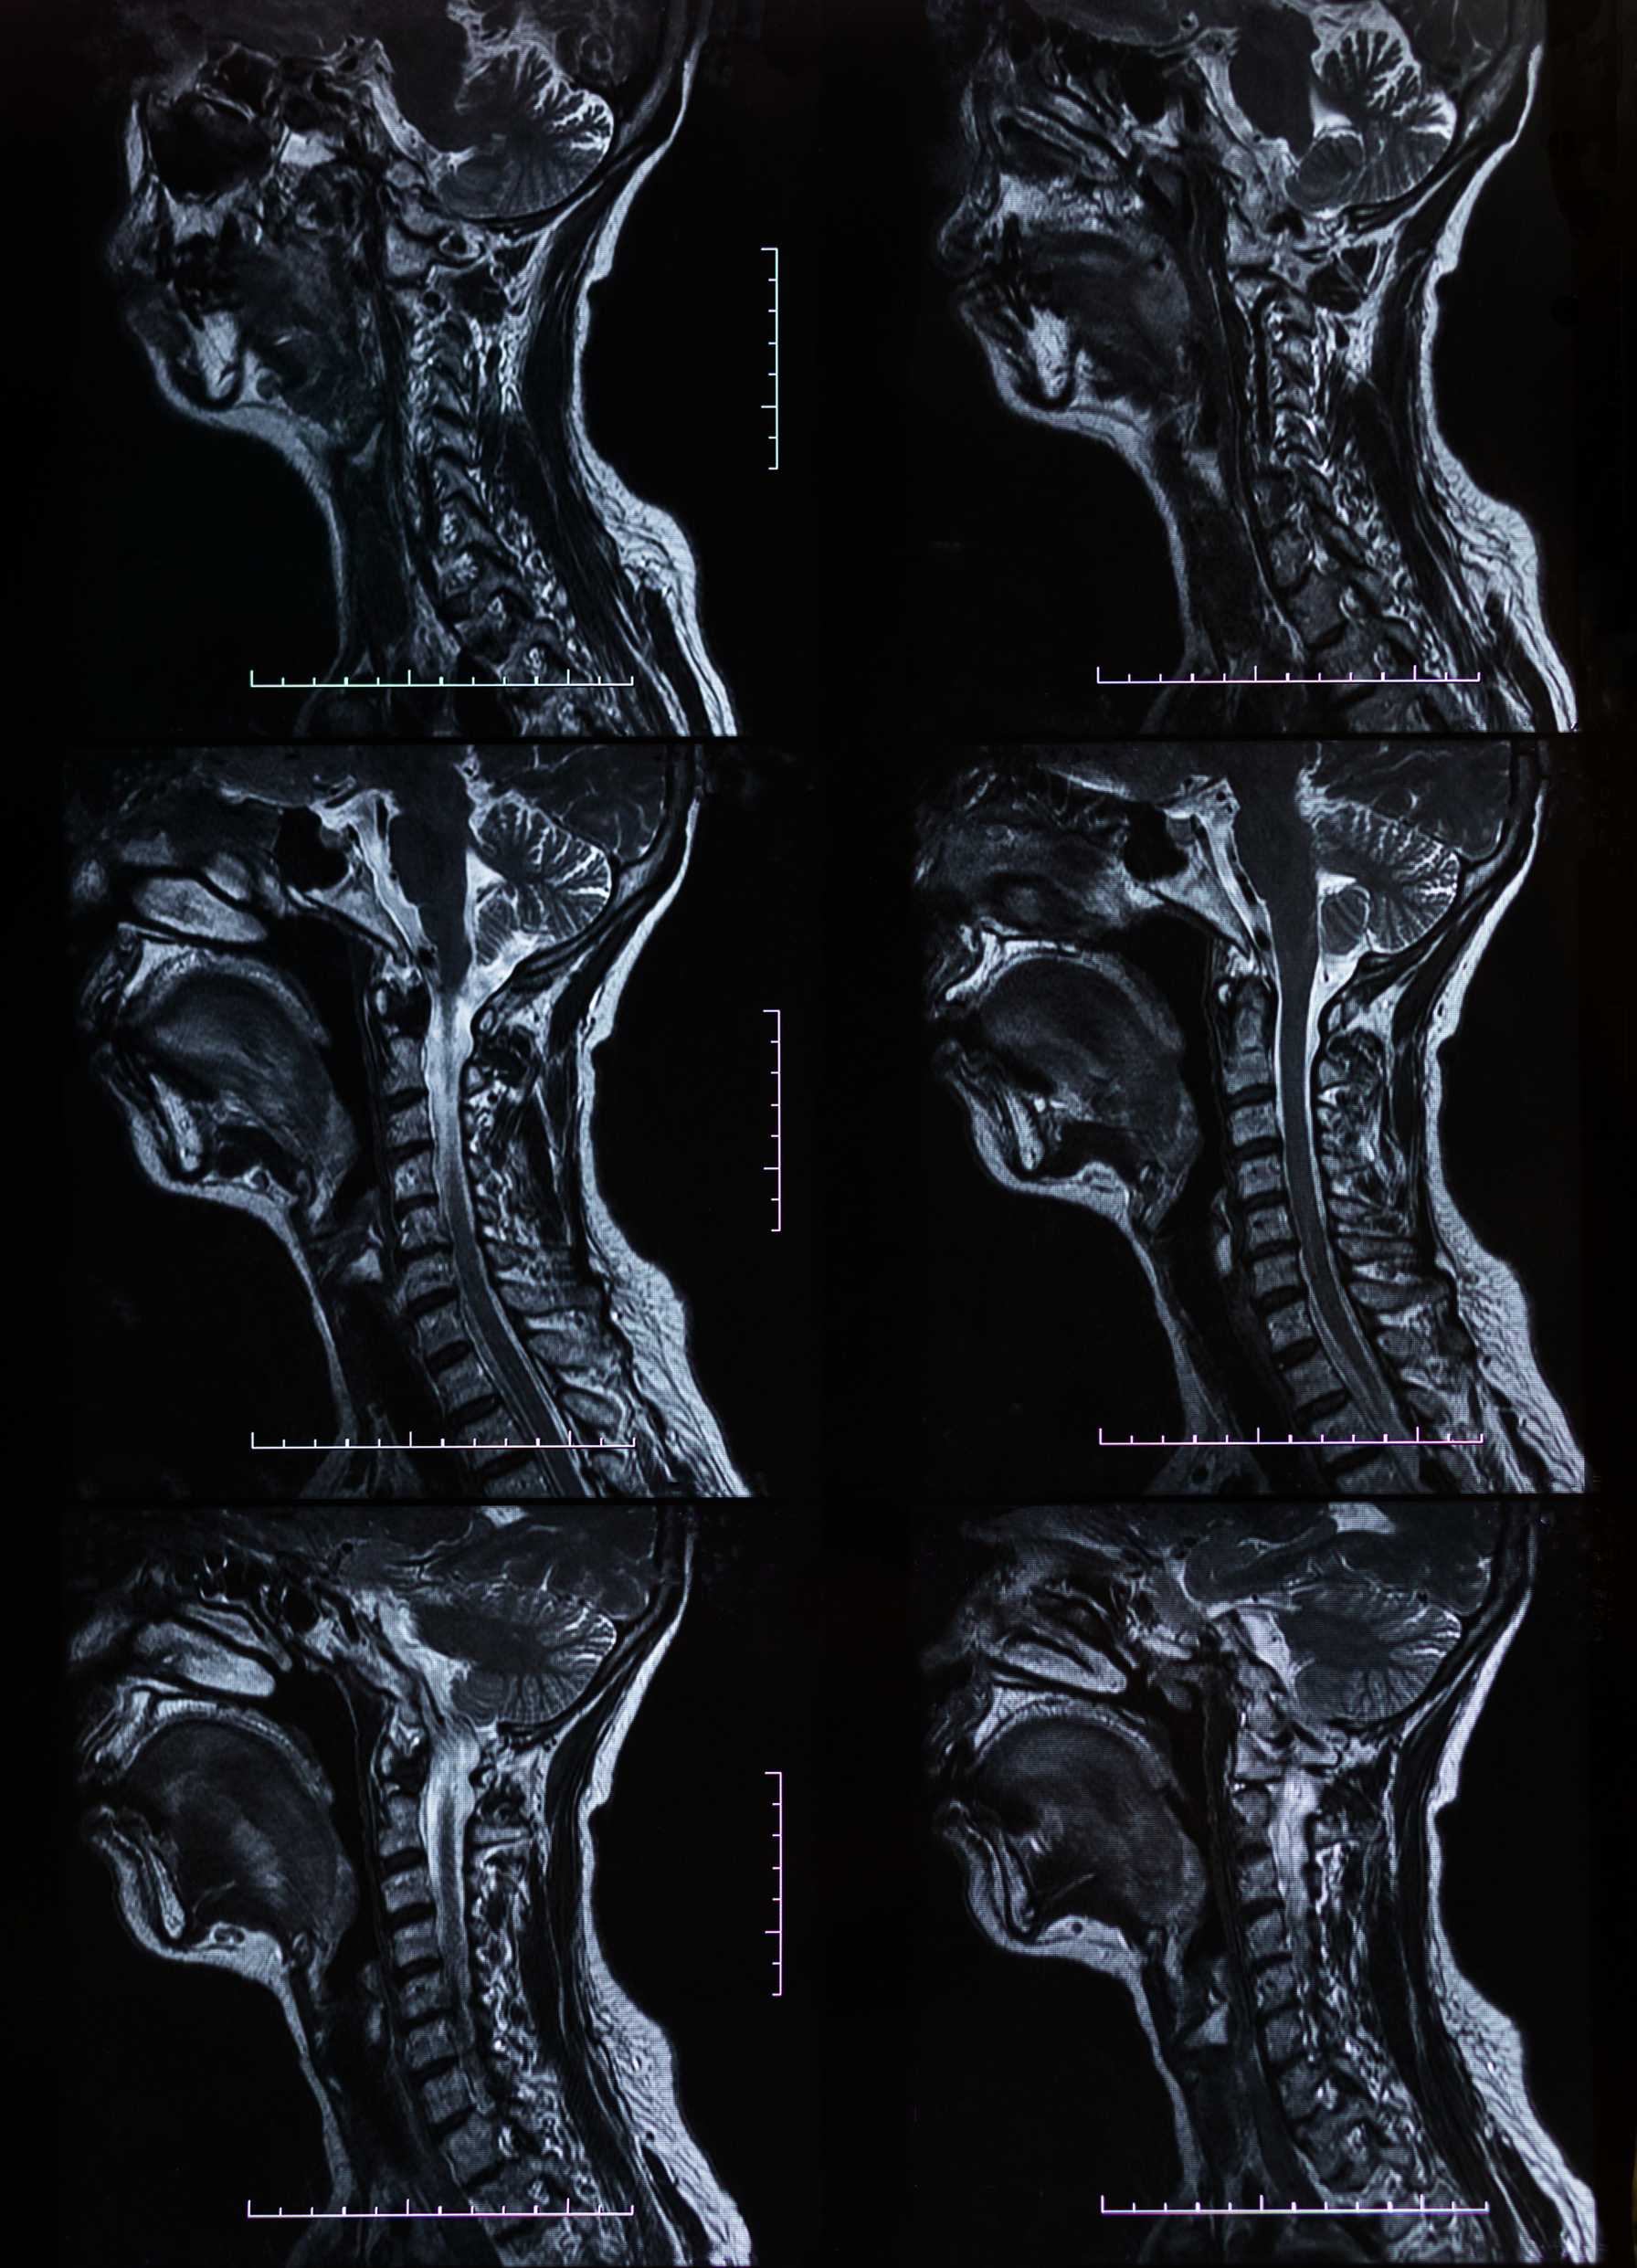

Molecular and Genomic Profiling of Head and Neck Tumors

- PI: Richard V. Smith, MD

- Sponsor: Montefiore Einstein